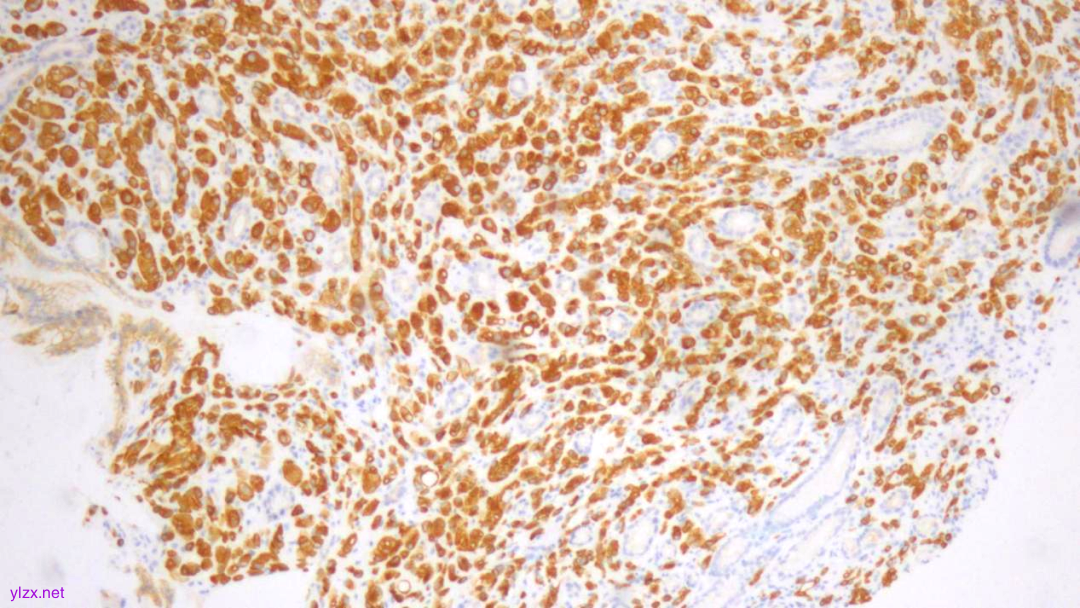

IHC结果:

CK(AE1/AE3)(+)、GATA3(+)、P120(浆+)、E-Cadherin(-)、CK7(+)、CK-H(+)、CAM5.2(+)、CK20(-)、CEA(poly)(-),P53(约40% 弱+),Ki-67(约1%+)

AE1/AE3(弥漫强+)

GATA-3(+)

P120(浆+)

E-Cadherin(-)

CK7(弥漫强+)

ki-67(个别细胞+)